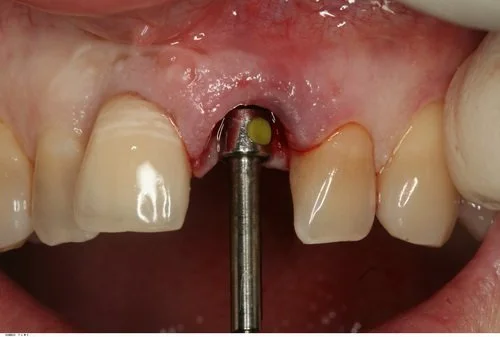

Tooth 21 was removed and due to excellent primary stability being achievable, with good interproximal bone height (Tarnow 1998) a Replace Select implant was placed immediately, with 40+ Ncm of torque being achieved. This allowed for placement of an immediate provisional restoration. The patient’s natural crown was used along with a titanium provisional abutment to construct a pleasing provisional restoration.

The abutment screw was torqued finger tight (~15 Ncm). The access cavity was then restored with cotton pellet and Cavit. The occlusion was adjusted to give no shim stock hold in ICP and no guidance in protrusion or lateral excursion.